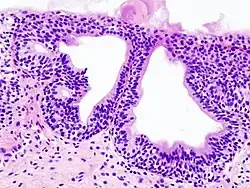

Cystitis glandularis

Cystitis glandularis is the transformation of mucosal cells lining the urinary bladder. They undergo glandular metaplasia, a process in which irritated tissues take on a different form, in this case that of a gland.[1] The main importance is in the findings of test results, in this case histopathology. They must distinguish a benign metaplastic change from the cancerous condition urothelial cell carcinoma.[2] It is a very common finding in bladder biopsies and cystectomies, and most often found in the trigone area. Cystitis glandularis lesions are usually present as small microscopic foci; however, occasionally it can form raised intramucosal or polypoid lesions. The cystitis glandularis lesions are within the submucosa.

Cystitis glandularis arises from and merges with Von Brunn's nests, which are groups of urothelial cells (cells of urinary tract) within the lamina propria and submucosa, formed from budding from the surface mucosa. They are considered normal. Cystitis cystica is a similar lesion to cystitis glandularis, where the central area of the Von Brunn's nests have degenerated, leaving cystic lesions. Other metaplastic entities in the urinary bladder include squamous metaplasia and nephrogenic adenoma.